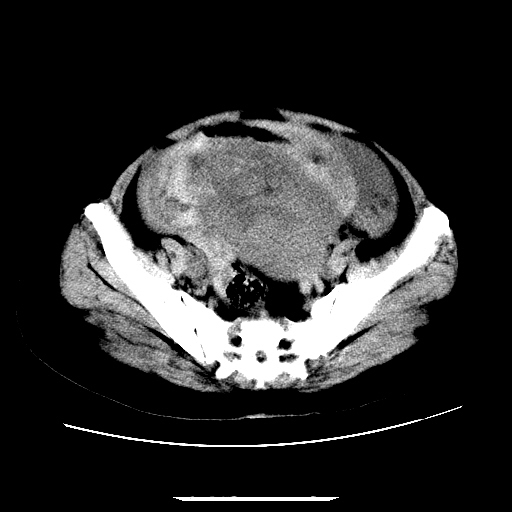

f,45y.怀孕4月晕倒,b超提示死胎,有手术结果,请展开讨论后明天告诉。

膈下-肠间隙内见气体密度影,子宫轮廓显示不清,宫腔-腹腔积液,首选考虑---子宫破裂出血。

1)宫腔妊娠。2)子宫破裂出血,腹腔及盆腔积血。

怀孕4个月晕倒,病史就这么简单?有没有腹痛呢?腹腔内有没有气体?窗宽太窄了脂肪组织与气体已不好分。如果有气体,那就是空腔脏器穿孔,如胃肠穿孔。如没有气体,就考虑子宫破裂或宫外孕破裂。正常怀孕子宫破裂很少见,有可能是宫外孕。极有可能是残角子宫怀孕破裂。腹腔怀孕破裂也有可能。

感谢同行们的高见。手术结果:子宫破裂出血。

我们的诊断是:腹、盆腔积液(考虑腹盆腔脏器破裂出血);宫腔妊娠。让人纳闷的是当时我们没有经验,现在回头看看分析:4月宫腔妊娠:1、洋膜囊不可能紧贴胎体这么小;2仔细看看子宫后壁肌层模糊不清;3腹、盆腔液体来源原因?4、45岁高龄妊娠有晕倒。由此可大胆诊断:宫腔妊娠子宫破裂出血。